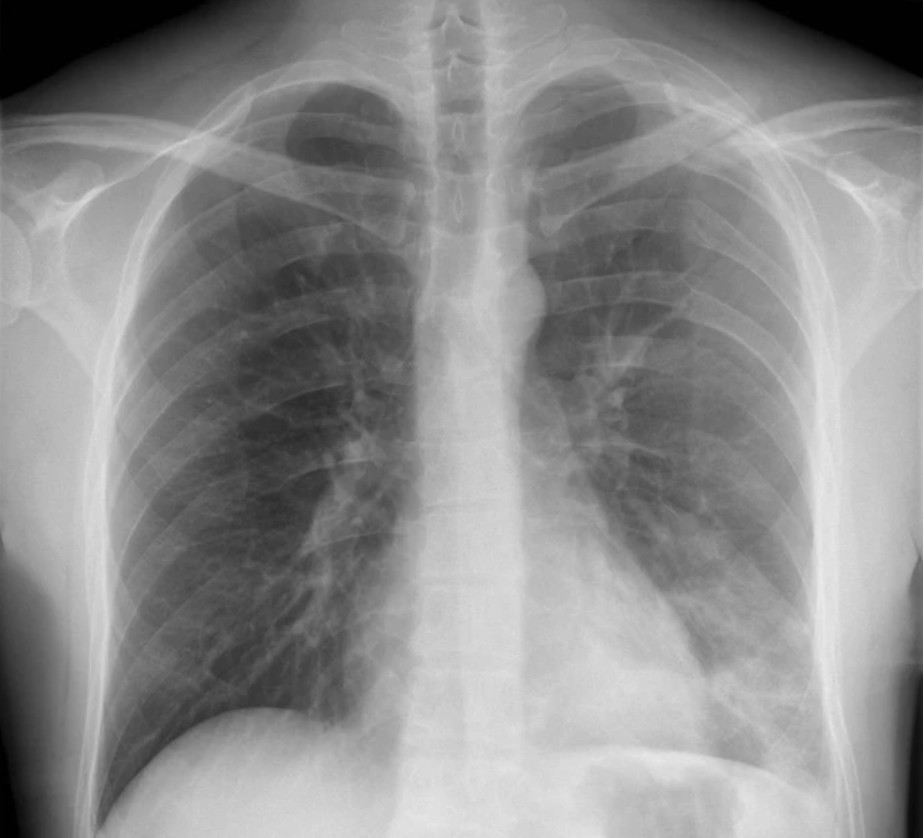

锁骨骨折视诊时,由于锁骨的浅表位置和相应的病史,可见典型姿态,可快速诊断。进一步的临床检查可通过视诊和触诊确定骨折部位。必须评估皮肤被刺穿的风险以及骨碎片导致血液循环障碍的风险。

由于疼痛症状,功能检查无法进行或明显受限,非必须进行。必须检查外周血液循环、运动功能和感觉功能,这可能提示伴随损伤。尤其在高速创伤情况下,应进行完整的体格检查。肺部听诊排除气胸。

伴随损伤:相邻的胸锁关节和肩锁关节也必须进行临床检查。外周脉搏质量、皮肤颜色或血肿的检查可能提示动脉或静脉血管损伤。与锁骨相关的血管损伤少见,但具有潜在的致命性。预计 1–3% 的锁骨骨折患者伴有血胸或气胸。其他相关损伤涉及胸锁关节、肩锁关节和颈椎。罕见情况下,也会出现锁骨下动、静脉和臂丛神经损伤。在高速和极高速创伤中,伴随损伤可能性大,所有骨折都必须进行伴随损伤检查。多项研究表明,外侧三分之一骨折可导致肩袖损伤,尤其部分撕裂(如下图)。此外,还可能发生肱二头肌长头腱损伤,例如滑车损伤或上盂唇从前到后损伤 。

左侧锁骨骨干骨折伴多发性肋骨骨折作为伴随损伤